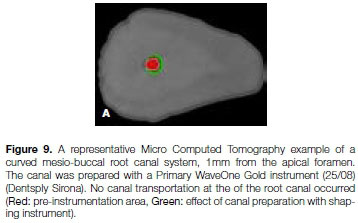

Figures 9 and 10 illustrate micro-computed tomographic images of two curved mesio-buccal root canal systems of extracted, maxillary first molar teeth at a level 1mm from the apical foramen. The example in Figure 9 shows minimal canal transportation after root canal preparation compared with that in Figure 10 which clearly shows an excessive amount of canal transportation.